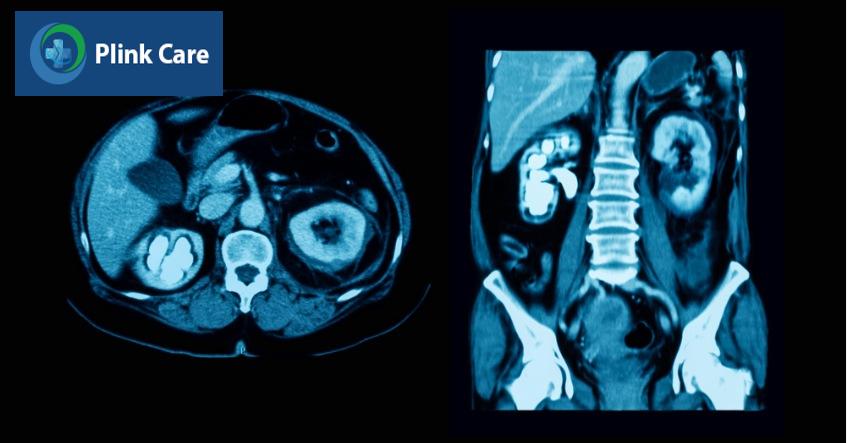

Bệnh thận ứ nước có nguy hiểm không? Biến chứng có thể gặp

Bệnh thận ứ nước có nguy hiểm không?

Có, bệnh thận ứ nước sẽ tiến triển nguy hiểm nếu không được điều trị kịp thời. Tuy nhiên, hầu hết trường hợp bệnh đều ở mức độ nhẹ đến trung bình và không gây ra ảnh hưởng nghiêm trọng đến sức khỏe. Ở một số trường hợp thận ứ nước nặng có thể làm tổn thương thận và dẫn đến suy thận.

Trong trường hợp thận ứ nước mạn tính, chức năng thận bị suy giảm, không có khả năng hồi phục, thậm chí dẫn đến suy thận. Tuy hầu hết các trường hợp đều ở mức độ nhẹ đến trung bình và không gây ra vấn đề sức khỏe nghiêm trọng, thế nhưng việc phát hiện bệnh ở giai đoạn muộn sẽ dễ dẫn đến những hệ lụy nguy hiểm, tăng nguy cơ biến chứng, thậm chí đe dọa tính mạng người bệnh. (1)